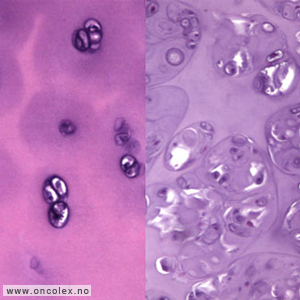

Lysmikroskopibilde av normal leddbrusk til venstre og lavgradig malignt kondrosarkom til høyre. |

Lysmikroskopibilde av høygradig malignt kondrosarkom. |